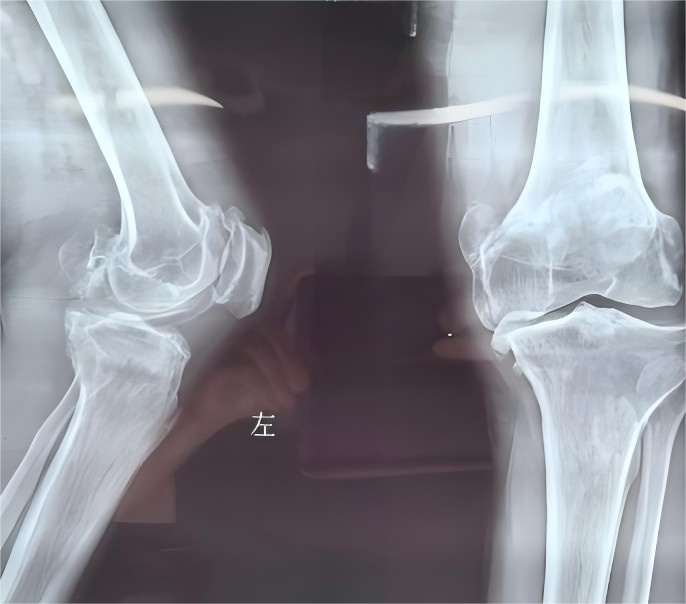

特點是:關(guān)節(jié)軟骨退化、骨質(zhì)增生,滑膜炎。主要表現(xiàn)為?膝關(guān)節(jié)疼痛、僵硬和活動受限?。常用的治療包括:理療,下肢力量練習(xí),膝關(guān)節(jié)矯形器(包括護膝,有些比護膝復(fù)雜一些),注射玻璃酸鈉等藥物,外敷藥物等。如果有輕度x型腿或o型腿,應(yīng)當(dāng)盡早使用膝關(guān)節(jié)矯形器。

骨關(guān)節(jié)炎是一種常見的關(guān)節(jié)疾病,尤其在中老年人群中高發(fā)。它會導(dǎo)致關(guān)節(jié)疼痛、僵硬和活動困難,嚴(yán)重影響日常生活。目前,我國40歲以上人群骨關(guān)節(jié)炎的總體患病率已高達46.3%,而且,隨著我國人口老齡化加劇,骨關(guān)節(jié)炎的患病率逐年上升。了解這種疾病的基本知識,掌握科學(xué)的預(yù)防和治療方法,對提高生活質(zhì)量至關(guān)重要。骨關(guān)節(jié)炎是關(guān)節(jié)軟骨退化引起的慢性疾病。關(guān)節(jié)軟骨就像關(guān)節(jié)的“緩沖墊”,隨著年齡增長或長期過度使用,軟骨逐漸磨損甚至消失,導(dǎo)致骨頭直接摩擦,引發(fā)疼痛、腫脹和活動受限。最常見的發(fā)病部位包括膝關(guān)節(jié)、髖關(guān)節(jié)、手指關(guān)節(jié)等。以下人群風(fēng)險較高:中老年人:尤其是40歲以上人群,年齡越大患病率越高。女性:女性患病率是男性的1.6倍,可能與激素變化有關(guān)。肥胖者:體重過重會增加關(guān)節(jié)負(fù)擔(dān)。關(guān)節(jié)受過傷的人:如骨折、韌帶損傷等。長期關(guān)節(jié)勞損者:如體力勞動者、運動員等。早期癥狀容易被忽視,但隨著病情加重,可能出現(xiàn):疼痛:初期活動后疼痛,休息緩解;后期可能持續(xù)疼痛甚至夜間痛醒。僵硬:早晨起床或久坐后關(guān)節(jié)僵硬,活動幾分鐘后好轉(zhuǎn)?;顒邮芟蓿宏P(guān)節(jié)活動范圍變小,如蹲下困難、上下樓梯疼痛。關(guān)節(jié)變形:晚期可能出現(xiàn)關(guān)節(jié)腫大、畸形(如手指關(guān)節(jié)結(jié)節(jié))。注意:如果出現(xiàn)上述癥狀,尤其是持續(xù)一個月以上,建議盡早就醫(yī)。醫(yī)生通常會結(jié)合以下方法:1.問診和體檢:了解疼痛特點,檢查關(guān)節(jié)活動度和壓痛情況。2.影像學(xué)檢查:X光:觀察關(guān)節(jié)間隙是否變窄、骨質(zhì)增生等。超聲或核磁共振(MRI):用于早期病變或復(fù)雜情況。3.對于一部分患者,還需要完善抽血化驗,與類風(fēng)濕關(guān)節(jié)炎、痛風(fēng)等其他風(fēng)濕病進行鑒別。治療目標(biāo)是緩解疼痛、保護關(guān)節(jié)功能。根據(jù)病情輕重,醫(yī)生會制定階梯化治療方案:1.基礎(chǔ)治療(適用于早期或預(yù)防)控制體重:減輕關(guān)節(jié)負(fù)擔(dān)。適度運動:選擇游泳、騎自行車、太極拳等低沖擊運動,增強肌肉力量。物理治療:熱敷、超聲波、電療等可緩解疼痛。輔助工具:使用拐杖、護膝等減少關(guān)節(jié)壓力。2.藥物治療外用藥物:如止痛貼膏、辣椒素藥膏等(需避免接觸眼睛)??诜幬铮横t(yī)生可能開具消炎止痛藥(如布洛芬、塞來昔布等),或保護軟骨的藥物(如雙醋瑞因、氨基葡萄糖)和抗焦慮抑郁藥物(度洛西汀等)。3.注射治療包括玻璃酸鈉注射、富血小板血漿(PRP)注射和臭氧關(guān)節(jié)內(nèi)注射治療等,需要在醫(yī)生的指導(dǎo)和建議下進行,建議嚴(yán)格限制每年關(guān)節(jié)腔注射時間和次數(shù),避免加重關(guān)節(jié)的損傷。4.微創(chuàng)介入治療包括射頻技術(shù)、關(guān)節(jié)鏡清理及關(guān)節(jié)腔灌洗,具有創(chuàng)傷小、操作安全、手術(shù)時間短、療效顯著、術(shù)后恢復(fù)快等優(yōu)點,為傳統(tǒng)保守治療失敗但不能或不愿接受手術(shù)治療的患者提供了額外的選擇。5.傳統(tǒng)療法包括練功、中藥內(nèi)服外敷、艾灸、拔罐療法、按摩、針灸、針刀等,不同的療法對骨關(guān)節(jié)炎的療效不同,“因病制宜”,以上治療建議到正規(guī)中醫(yī)院進行,切忌盲目相信“祖?zhèn)髌健?,或在沒有正規(guī)資質(zhì)的按摩店治療。6.手術(shù)治療對于以上治療后效果仍不佳的患者,可以考慮外科手術(shù)治療。1.保護關(guān)節(jié)的小習(xí)慣避免長時間蹲跪、爬山、提重物。注意關(guān)節(jié)保暖,尤其是秋冬季節(jié)。穿軟底鞋或使用鞋墊,減少行走沖擊。必要時可以使用輔助器具,減輕關(guān)節(jié)負(fù)擔(dān)。2.科學(xué)鍛煉強化肌肉:靠墻靜蹲、直腿抬高等動作可增強膝關(guān)節(jié)周圍肌肉。柔韌性訓(xùn)練:每天拉伸關(guān)節(jié),保持靈活度。3.飲食調(diào)理多吃富含鈣和維生素D的食物(如牛奶、魚類、綠葉蔬菜)。適量補充Omega-3脂肪酸(如深海魚、堅果),有助于抗炎。4.心理調(diào)節(jié)疼痛可能引發(fā)焦慮或抑郁,可通過社交、興趣愛好或心理咨詢緩解壓力。不要盲目用藥:長期自行服用止痛藥可能傷胃、傷腎,需遵醫(yī)囑。警惕“偏方”:某些宣稱“根治骨刺”的療法缺乏科學(xué)依據(jù),可能延誤病情。定期復(fù)查:即使癥狀緩解,也應(yīng)定期檢查,監(jiān)測關(guān)節(jié)健康。骨關(guān)節(jié)炎雖無法徹底治愈,但通過科學(xué)管理和積極治療,完全可以控制癥狀、延緩進展。關(guān)鍵在“早發(fā)現(xiàn)、早干預(yù)”,別讓關(guān)節(jié)疼痛成為生活的絆腳石!參考文獻:中國骨關(guān)節(jié)炎診療指南專家組,中國老年保健協(xié)會疼痛病學(xué)分會,等.中國骨關(guān)節(jié)炎診療指南(2024版)[J].中華疼痛學(xué)雜志,2024,20(03):323-338.

來源:上海六院骨科歐陽元明歡迎分享本文,轉(zhuǎn)載請保留出處!膝關(guān)節(jié)關(guān)節(jié)內(nèi)游離體,又稱“關(guān)節(jié)鼠”。指在膝關(guān)節(jié)內(nèi),某些壓力骨骺的凸面可在外力反復(fù)作用下發(fā)生缺血性壞死、剝脫,在關(guān)節(jié)內(nèi)游離的軟骨或骨軟骨碎片。這也是一種常見的膝關(guān)節(jié)病。關(guān)節(jié)內(nèi)游離體可來自軟骨、骨軟骨或滑膜,可以是完全游離,也可以還有軟組織束帶相連。臨床上,膝關(guān)節(jié)游離體常出現(xiàn)關(guān)節(jié)交鎖現(xiàn)象。由于較小的游離體被夾擠在關(guān)節(jié)面之間,則出現(xiàn)突發(fā)關(guān)節(jié)交鎖現(xiàn)象。出現(xiàn)時,會有劇烈疼痛,且交鎖體位常不固定(有時屈曲位,不能伸;有時伸直位,不能屈)。會因膝關(guān)節(jié)滑膜受到機械刺激而出現(xiàn)關(guān)節(jié)腫脹、積液,膝部軟弱無力,或因游離體游到表淺部而觸及到可移動的包塊。此外,在交鎖解鎖時,患者可以聽到或感到響聲、錯動感,有的還可能以引起跪跌現(xiàn)象。哪些病會出現(xiàn)游離體?1、剝脫性骨軟骨炎;2、骨關(guān)節(jié)炎;3、關(guān)節(jié)內(nèi)骨軟骨骨折;4、滑膜軟骨瘤病.關(guān)節(jié)腔內(nèi)游離體多為中老年人群,病程較長,常伴隨膝骨關(guān)節(jié)炎等退變性疾病.需要做什么樣的檢查?1、X線是關(guān)節(jié)內(nèi)游離體首選檢查:含有骨及軟骨組織的游離體,X線下可顯影。單純的軟骨組織形成的游離體,X線不顯影。2、CT:CT是對X線的有力補充,三維重建CT,更立體的幫助術(shù)前評估游離體的大小、數(shù)目及位置。3、MRI:MRI可以顯影軟骨游離體,有助于術(shù)前評估。此外,還可以對關(guān)節(jié)的軟骨損傷軟骨下骨壞死,半月板韌帶損傷做出評估。4、關(guān)節(jié)鏡檢:關(guān)節(jié)鏡檢同樣是診斷關(guān)節(jié)內(nèi)游離體的金標(biāo)準(zhǔn),可以發(fā)現(xiàn)一些CT或MRI不能很好顯影的游離體,并且在明確診斷的同時可以進行相應(yīng)的外科治療。如何進行治療?1、保守治療:(1)消除疼痛、限制活動:患者可以利用護膝進行保護,還可采用牽引、服用止痛藥等治療方法;(2)消除腫脹:采用局部熱敷、理療;(3)手法治療:通過屈伸復(fù)位法、推拉復(fù)位法等手法治療解除交鎖;(4)關(guān)節(jié)穿刺:抽出積液,注射玻璃酸鈉液,改善癥狀。2、手術(shù)治療:包括關(guān)節(jié)鏡手術(shù)清除游離體、手術(shù)切開徹底清除關(guān)節(jié)內(nèi)游離體及破碎的軟骨等。由于關(guān)節(jié)鏡手術(shù)創(chuàng)傷小、效果好,一些條件較好的患者可選擇此種治療方法。歐陽元明(上海市第六人民醫(yī)院國家骨科中心關(guān)節(jié)外科主任醫(yī)師,醫(yī)學(xué)博士,博士研究生導(dǎo)師)上海交通大學(xué)醫(yī)學(xué)院畢業(yè),從事臨床工作20多年,主攻關(guān)節(jié)外科。曾在韓國首爾,德國慕尼黑,加拿大及香港進修學(xué)習(xí),掌握先進關(guān)節(jié)置換手術(shù)及關(guān)節(jié)鏡技術(shù)。年均手術(shù)量1000臺左右。